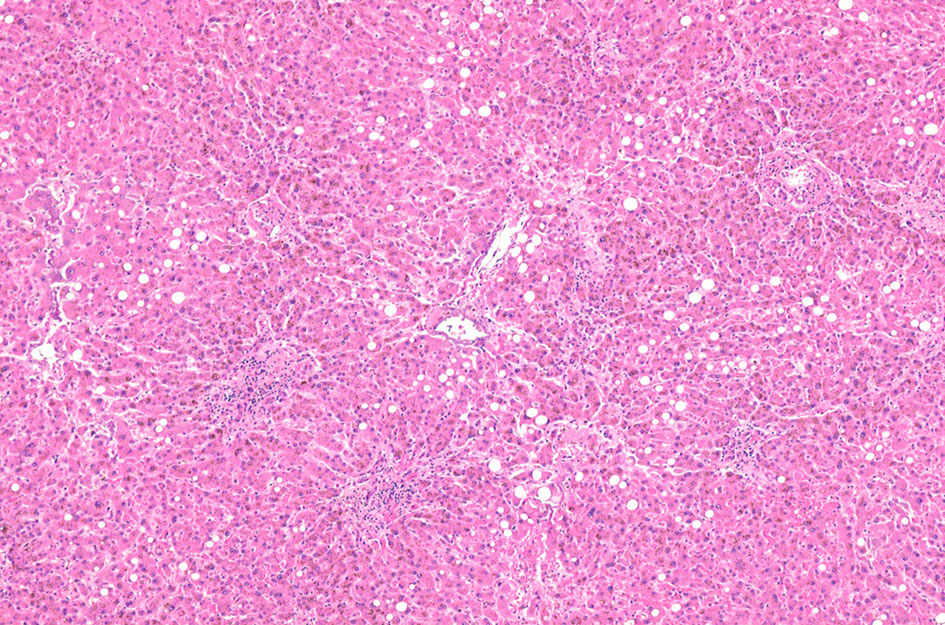

肝ヘモジデローシス 70歳代男性 胃癌術後B-II胃全摘術後